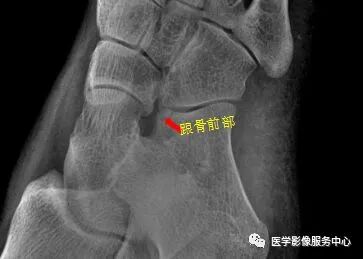

右足斜位示 右侧跟骨前部见骨折透亮线,右跟骨前部骨折。